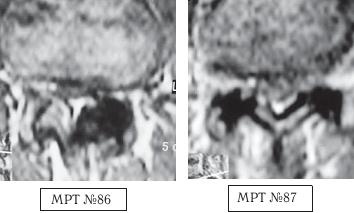

На МРТ № 86 наблюдается кровоизлияние (тёмное пятно на МРТ) в полость левого дугоотростчатого сустава — как следствие после лечения у мануального терапевта, который пытался «вправить выпавший диск».

На МРТ № 87 наблюдаются кровоизлияния в полости обеих дугоотростчатых суставов. Этот случай связан уже с другим пациентом, другим мануальным терапевтом, однако с тем же неутешительным результатом — снова кровоизлияние!

К сожалению, такие осложнения после мануальной терапии встречаются довольно часто. Их причина банальна — всего лишь попытка мануального терапевта устранить у пациента так называемую сублюксацию или «функциональный блок». Зачастую результат такого воздействия — кровоизлияние в полость травмированных дугоотростчатых суставов. Напомню, что внутренний слой суставной капсулы дугоотростчатых суставов имеет множество синовиальных ворсинок, богатых кровеносными сосудами. После травмы, когда кровь заполняет полость суставов, у пациента возникает боль, ограничение и болезненность движений вплоть до утраты способности пациента самостоятельно передвигаться.